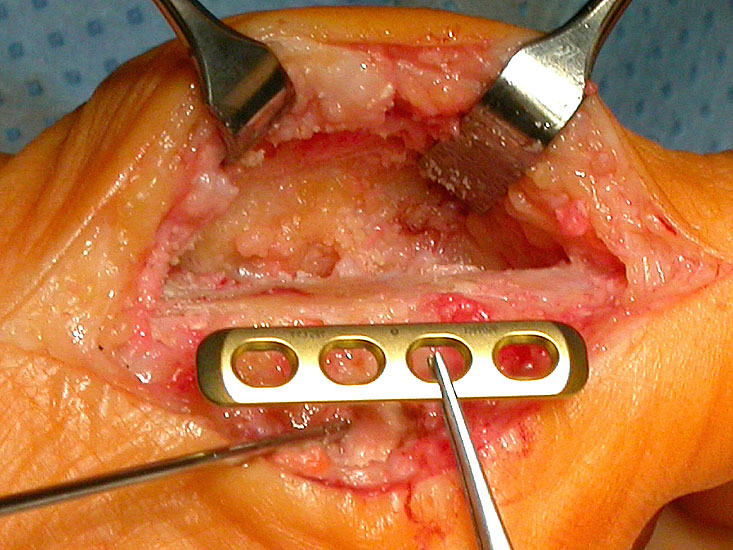

Kapsuläre Interpositionsarthroplastik nach Hamilton 31:

Zuerst erfolgt das Darstellen der Gelenkkapsel über einen medialen Zugang mit Längsinzision der Kapsel mittig sowie Ablösen des Kapselgewebes periostal dorsal und plantar vom Grundglied und dem Os metatarsale I. Dann wird mit der oszillierenden Säge die Cheilektomie  am Metatarsale-I-Kopf und die Resektion von maximal 25% der Basis des Grundgliedes vorgenommen. Hierbei wird die M. flexor hallucis brevis-Sehne durchtrennt und vorerst belassen. Die Gelenkkapsel wird zusammen mit der M. extensor hallucis brevis-Sehne mobilisiert und nach distal in den Gelenkspalt transferiert. Die M. flexor hallucis brevis-Sehne und die M. extensor hallucis brevis-Sehne werden im Gelenkspalt miteinander vernäht und die Kapsel mit der Umgebung refixiert. Es erfolgt eine temporäre Stabilisierung des Gelenkes mit einem doppelspitzen Kirschnerdraht in inside-outside Technik.